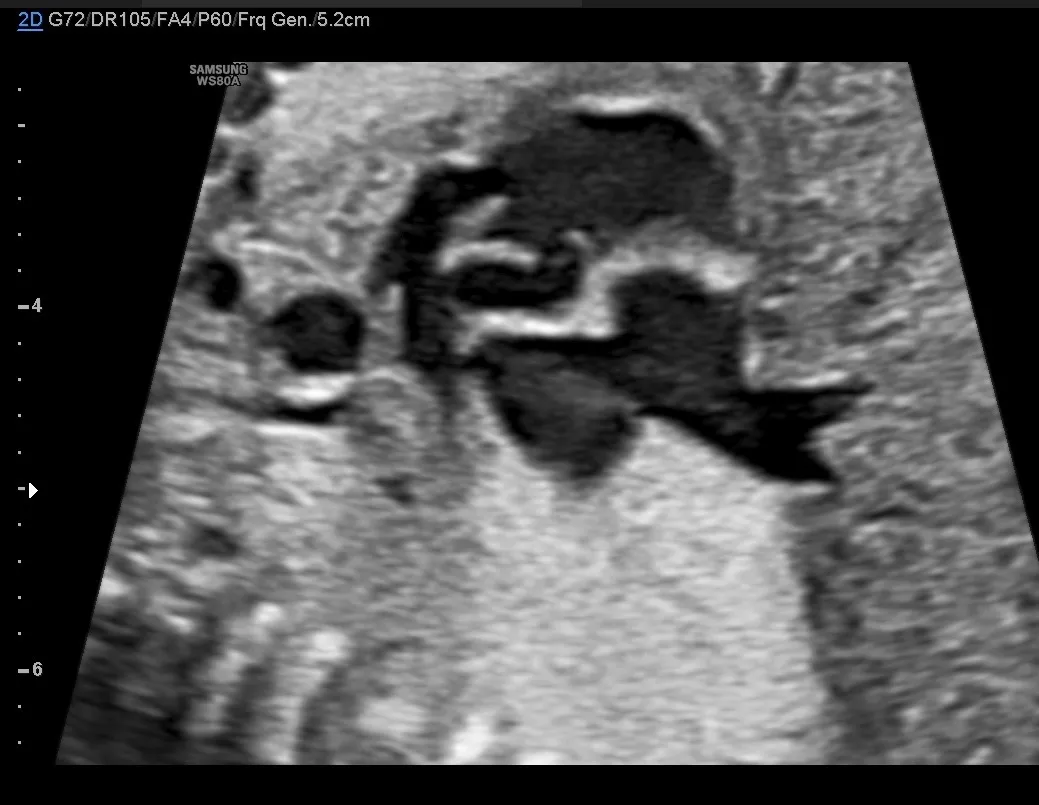

It's classical case of Tetralogy of Fallot.

Prenatally only three features of TOF are seen:

• perimembranous VSD,

• anterior deviation of the aorta and

• small pulmonary artery.

The fourth feature of TOF, right ventricular hypertrophy, is seen only postnatally.

The four-chamber view is usually normal, as the VSD is located in the memebranous part of the septum, except when TOF is associated with AVSD.

The cardiac axis is often displaced leftwards

• The first great artery (aorta) arises from the centre of the heart and sits astride the crest of the ventricular septum (overriding aorta) above the VSD.

• The great arteries are normally related but the pulmonary artery is smaller than the usually enlarged aorta.